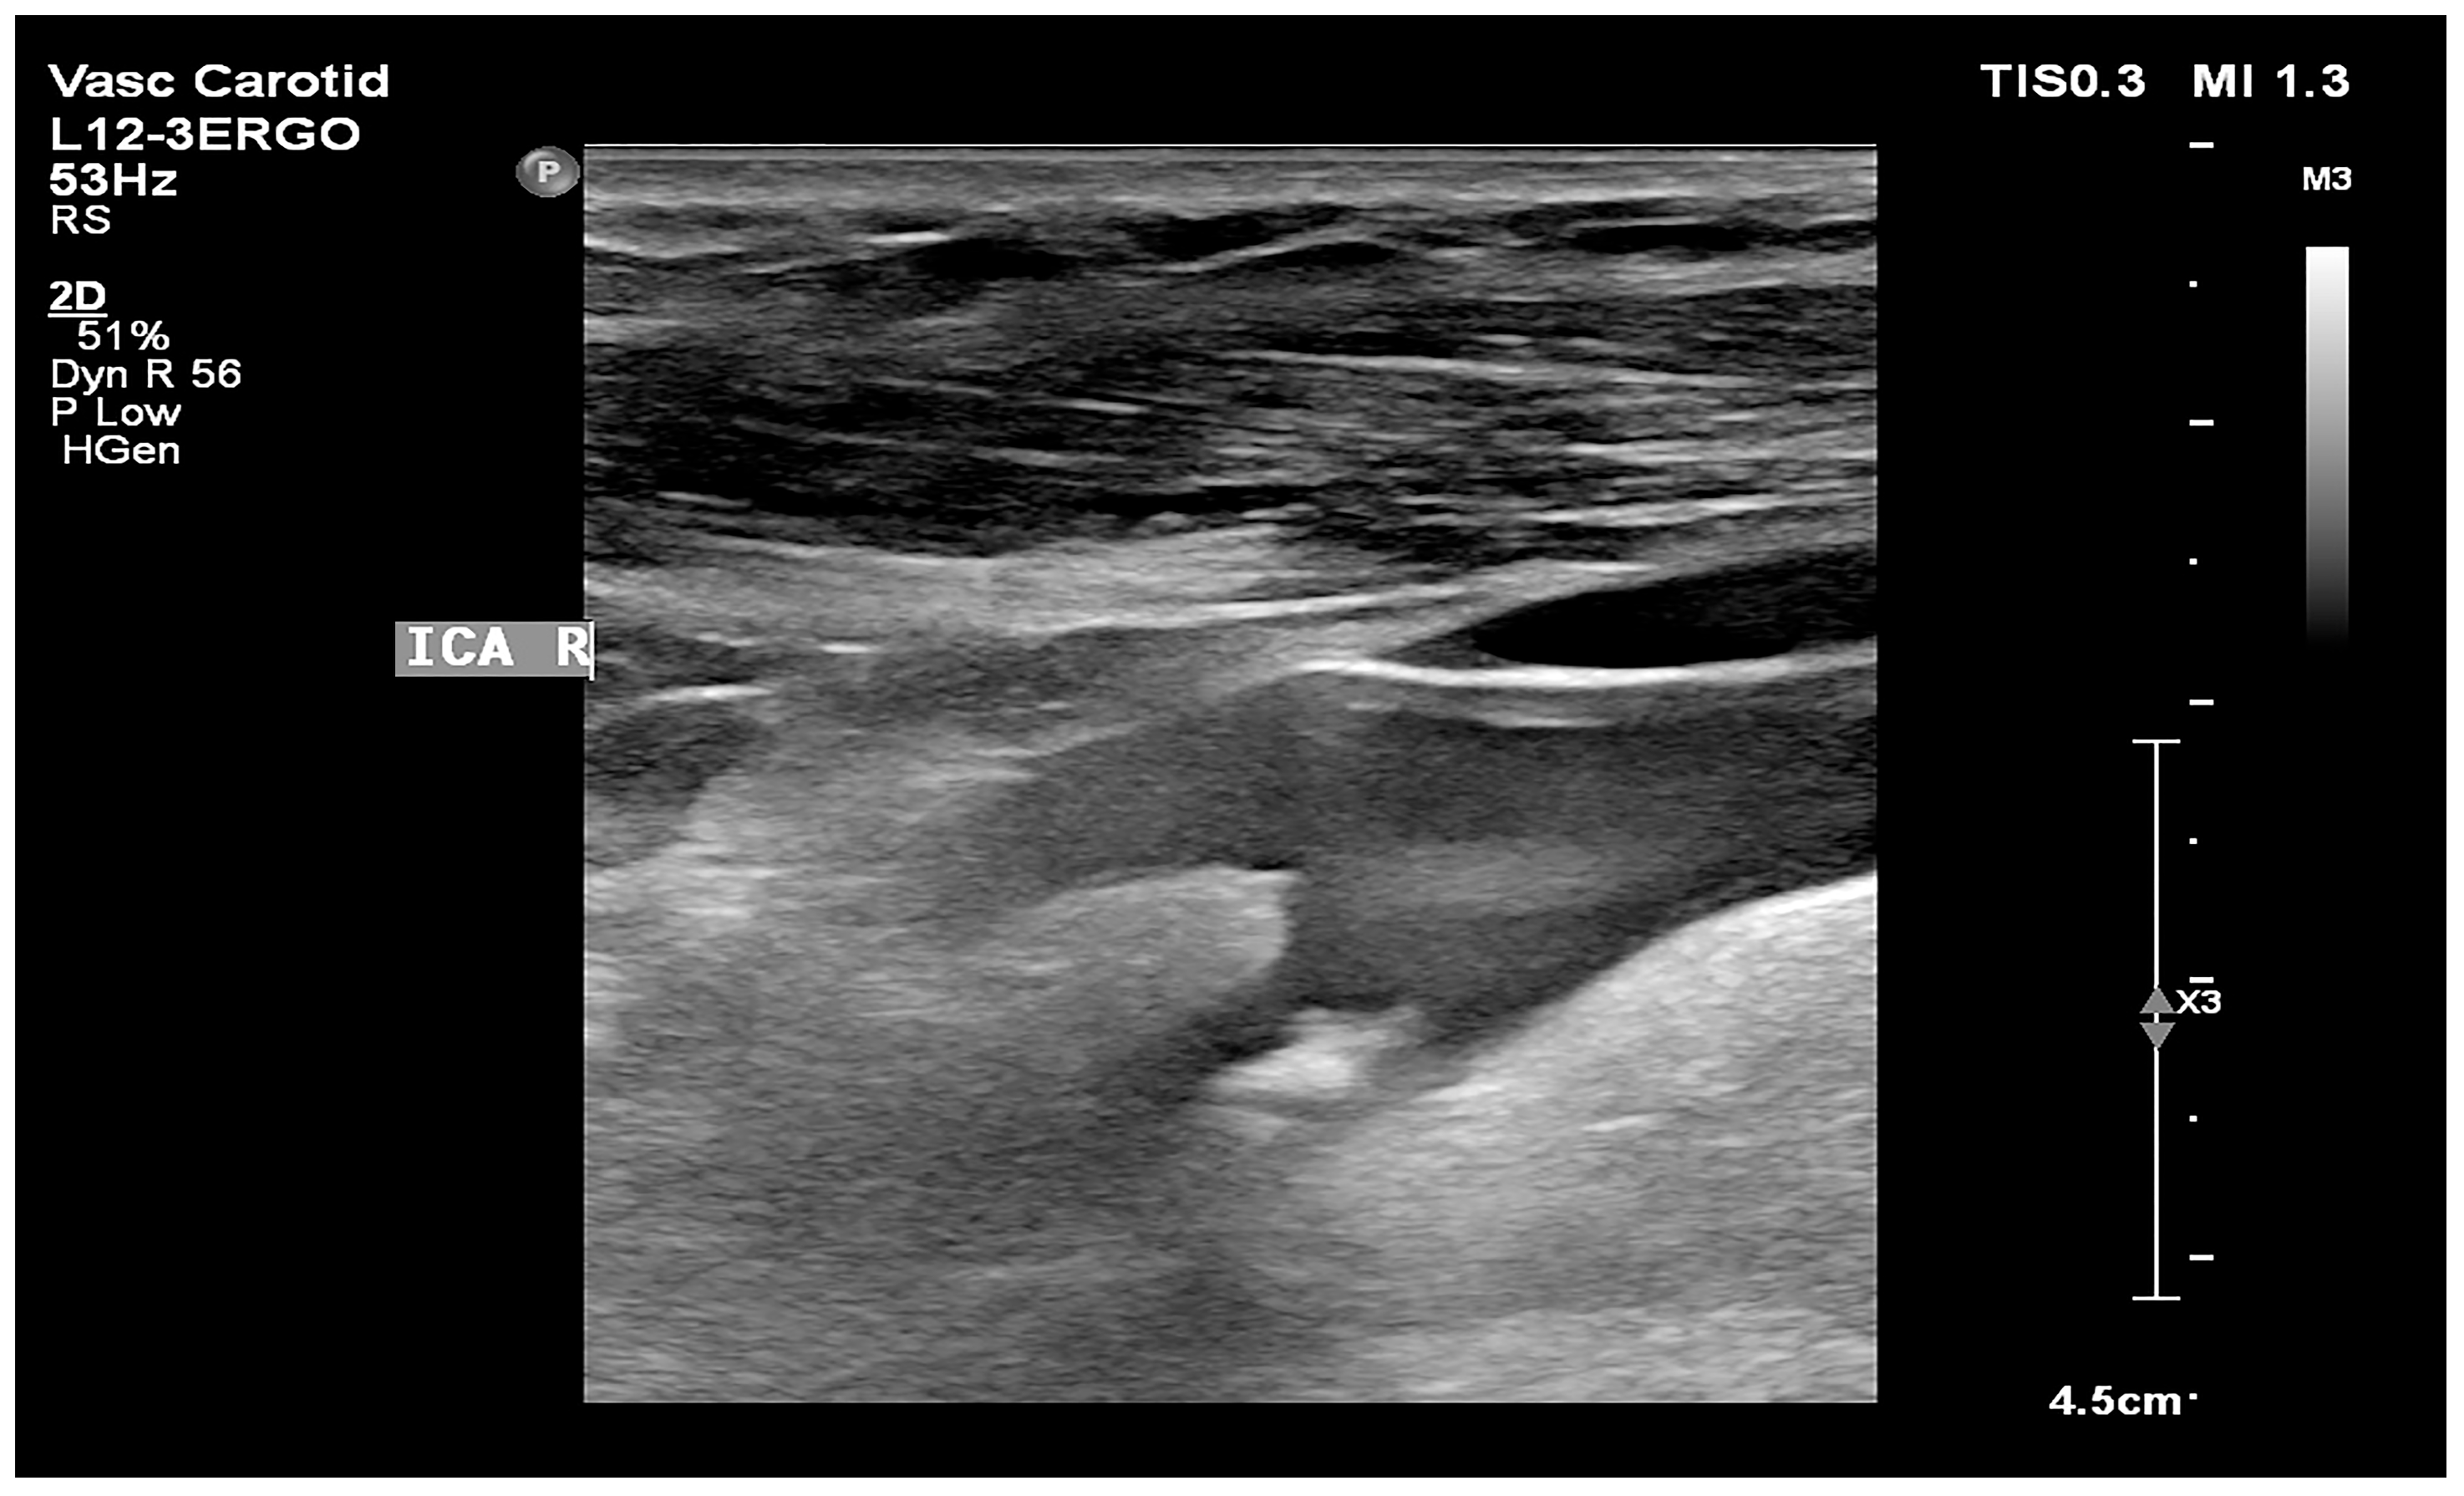

- Atherosclerotic plaque—during the ultrasound examination, the best possible image projection in B-mode presentation was selected with the entire atherosclerotic plaque visible—the image was not enlarged or brightened—according to the accepted standardization. The image of the plaque was recorded on a photograph. Then, to assess the atherosclerotic plaque, images from the ultrasound examination were used to analyze its structure on the GSM scale.

- Images of the visible atherosclerotic plaque in the carotid artery.

2.3.2. Image Standardization

2.3.3. Calculation of the GSM Value of Atherosclerotic Plaques